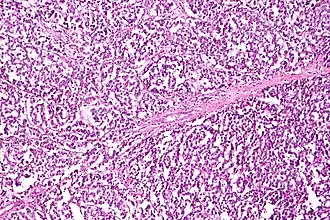

| Micrograph of a mucinous ovarian carcinoma stained by H&E | |

Mucinous

Mucinous tumors include mucinous adenocarcinoma and mucinous cystadenocarcinoma.[29]

Mucinous adenocarcinoma

Mucinous adenocarcinomas make up 5–10% of epithelial ovarian cancers. Histologically, they are similar to intestinal or cervical adenocarcinomas and are often actually metastases of appendiceal or colon cancers. Advanced mucinous adenocarcinomas have a poor prognosis, generally worse than serous tumors, and are often resistant to platinum chemotherapy, though they are rare.[29]